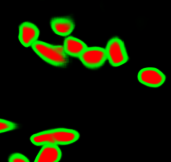

As an essential part of digital pathology, histopathology image analysis is playing increasingly important role in cancer diagnosis, which can provide direct and reliable evidence to diagnose the grade and type of cancer. This paper deals with nuclei segmentation, an important step in histopathological image analysis. The purpose of nuclei semgentation is not only counting the number of nuclei but also obtaining the detailed information of each nucleus. So unlike nuclei detection, here the outputs are the contour of each nucleus instead of only the position of their central points. Hence we can exactly extract each nucleus from the image and make it available for further analysis. For example, the features of the individual nucleus and the distribution of nuclei clusters can be used to grade and classify status of breast cancers [3, 4]. Because of appearance variation such as color, shape, and texture, nuclei segmentation from histopathological images could be very challenging, as illustrated in Fig.1, in which it is very challenging even for human to recognize and segment all nuclei within the images. Fig.1(a) and Fig.1(b) illustrate two histopathological images from different organs. Fig.1(c) and Fig.1(d) are two histopathological images from same organ but have different cancer grade.

The task of nuclei segmentation can be roughly divided into two stages: the first stage is extracting the foreground(nuclei), the second stage is segmenting the connected foreground area into separated nuclei and finding out the boundary of each nucleus. Our method intends to merge these two steps by extracting the nuclei and their edges at the same time. That is the reason why it is named ”nuclei-boundary(NB) model”. As shown in Fig.3, the output of the NB model has three channels, each has the same height and width with the input image. Its values represent the probabilities of each pixel being , or class, respectively. The manual annotation for our segmentation problem is the boundary of each nucleus. A pixel belonging to the class means that it is on or inside an annotated boundary and within 2 pixel from the boundary. Pixels of the class are those that are inside annotated boundary but are not pixels. Correspondingly, the output can be regarded as an RGB image and the estimated maps of the , and are represented by red, green and blue, respectively, as shown in Fig.3. To generate the ternary mask for training, we apply a morphology operator to each nucleus to obtain the pixels, and then subtract pixels from the nucleus to get pixels.